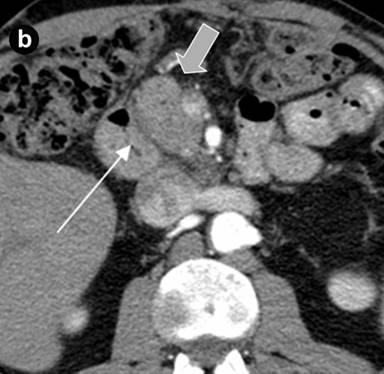

A 43-year-old man with abdominal pain of a one year duration, nausea, vomiting, weight loss and intermittent jaundice was referred to the Hospital of the Russian Federal Security Service, Moscow, Russia, with a clinical diagnosis of chronic pancreatitis. The patient had a history of previous extensive small bowel resection; one year previously he had been operated on for acute pancreatitis with abdominal draining and a cholecystectomy. The epigastrium was mildly sensitive on physical examination. The laboratory findings were normal, except for a slight increase in the bilirubin level (40 µmol/L; reference range: 3.5-19.0 µmol/L). Abdominal US showed diffuse changes of the liver and pancreas. On computed tomography (Figure 6) and magnetic resonance imaging (Figure 7), a thick-walled cystic lesion 4x4.5 cm which had infiltrated the medial wall of the second part of the duodenum was observed against the background of the minimally changed pancreatic structure with pancreatic and common bile duct dilation,. Endosonography revealed a solid and septated cystic lesion mainly located in the submucosa of the narrowed second portion of the duodenal wall.

Figure 6. Arterial phase of multi-detector computed tomography before (a.) and 6 months after (b.) the pancreas-preserving resection of the second portion of the duodenum with the jejunal interposition (Case #2). a. There is a septated cystic structure (thin arrow) in the medial duodenal wall with prominent inflammation and fibrosis around the duodenum and pancreatic head (thick arrow). b. Neoduodenum (thin arrow) and pancreatic head (thick arrow) without signs of inflammation or fibrosis. |